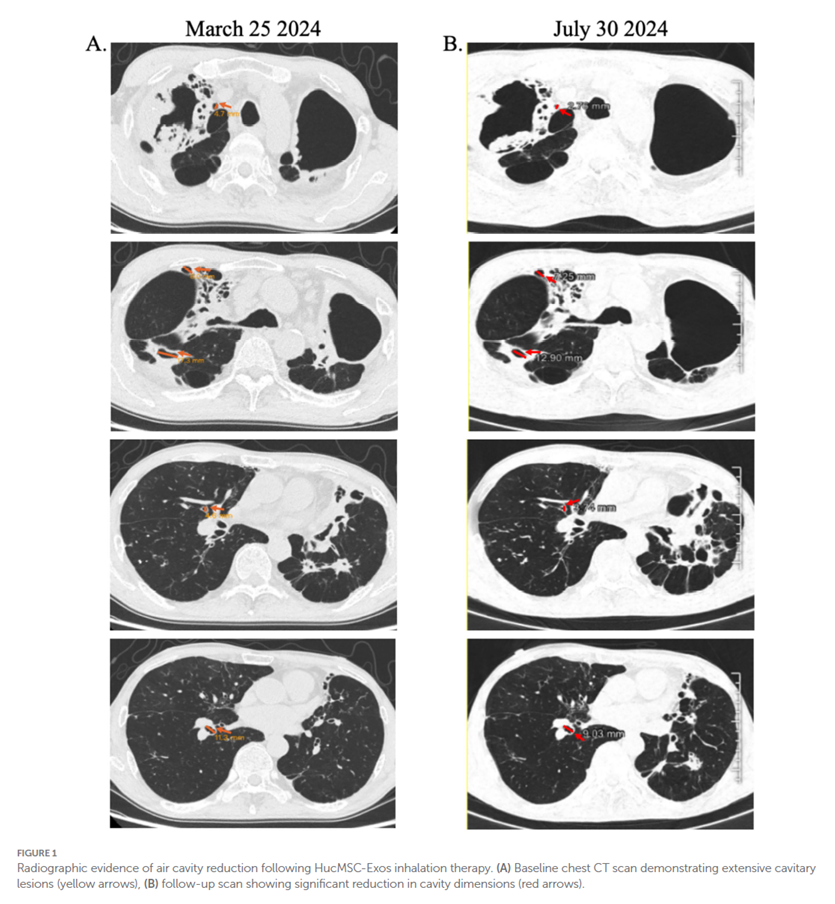

(3)影像学显示出逆转:该患者在治疗后,胸部CT显示,与基线相比,可见肺部空腔明显缩小,如下图所示。

图片来自文献[1]